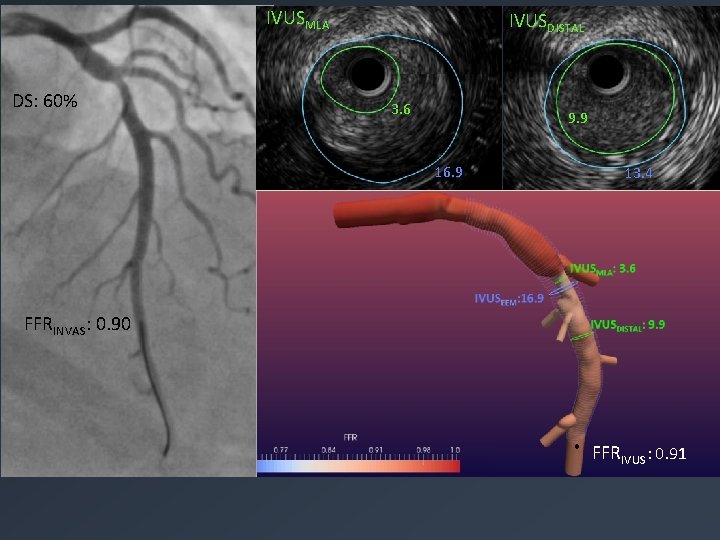

IVUSMLA DS: 60% IVUSDISTAL 3. 6 9. 9 16. 9 13. 4 FFRINVAS: 0. 90 FFRIVUS: 0. 91